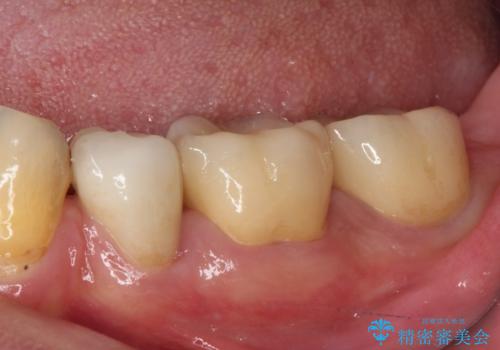

虫歯を取り除き、仮歯を装着した時点でしみる感覚は改善されました。

オールセラミッククラウン装着後も経過は良好です。